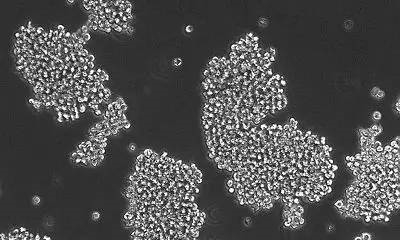

еңЁиҝҷдёҖз ”з©¶дёӯ�пјҢ�пјҢпјҢ�пјҢ�пјҢ�пјҢ�пјҢRaabeеҚҡеЈ«зӯүдәәд»ҺжӮЈиҖ…дҪ“еҶ…з–Ҹж•ЈеҮәдәҶзҷҢз»Ҷиғһ�пјҢ�пјҢпјҢ�пјҢ�пјҢ�пјҢ�пјҢ并且让其жҺҘеҸ—иҚҜзү©еҲәжҝҖгҖӮгҖӮ�гҖӮ�гҖӮ�гҖӮ�гҖӮ�гҖӮж•ҲжһңжҳҫзӨә�пјҢ�пјҢпјҢ�пјҢ�пјҢ�пјҢ�пјҢTAK228иғҪеӨҹйҷҚдҪҺDIPGз»Ҷиғһзҡ„еўһж®–�пјҢ�пјҢпјҢ�пјҢ�пјҢ�пјҢ�пјҢ并且дјҡйҖ жҲҗ6%з»Ҷиғһзҡ„ж®’е‘ҪгҖӮгҖӮ�гҖӮ�гҖӮ�гҖӮ�гҖӮ�гҖӮ

然иҖҢ�пјҢ�пјҢпјҢ�пјҢ�пјҢ�пјҢ�пјҢеҪ“дёҺж”ҫз–—иҝһзі»еңЁдёҖиө·ж—¶�пјҢ�пјҢпјҢ�пјҢ�пјҢ�пјҢ�пјҢдҪңиҖ…еҸ‘жҳҺTAK228зҡ„иҒ”еҗҲжІ»з–—иғҪеӨҹеўһејәйҖҡдҫӢеҢ–з–—жқҖдјӨDIPGзҡ„дёҖеҖҚзҡ„ж•ҲжһңгҖӮгҖӮ�гҖӮ�гҖӮ�гҖӮ�гҖӮ�гҖӮе…ідәҺAT/RTsиҖҢиЁҖ�пјҢ�пјҢпјҢ�пјҢ�пјҢ�пјҢ�пјҢиҜҘиҚҜзү©иғҪеӨҹиө·еҲ°зӣёдјјзҡ„жҠ‘еҲ¶еўһж®–зҡ„ж•Ҳжһң�пјҢ�пјҢпјҢ�пјҢ�пјҢ�пјҢ�пјҢеҗҢж—¶иғҪеӨҹеӨ§е№…еўһй«ҳеўһиҝӣз»ҶиғһеҮӢдәЎзҡ„иғҪеҠӣгҖӮгҖӮ�гҖӮ�гҖӮ�гҖӮ�гҖӮ�гҖӮд№ӢеҗҺ�пјҢ�пјҢпјҢ�пјҢ�пјҢ�пјҢ�пјҢзңӢжҲҗиҖ…е°ҶTAK228дёҺеҢ–з–—иҚҜзү©cisplatinиҝһзі»дҪҝз”Ёж—¶�пјҢ�пјҢпјҢ�пјҢ�пјҢ�пјҢ�пјҢе°Ҹйј зҡ„еӯҳжҙ»ж—¶й—ҙиғҪеӨҹ延伸еҝ«иҰҒдёҖдёӘжңҲ�пјҢ�пјҢпјҢ�пјҢ�пјҢ�пјҢ�пјҢиҖҢеҚ•зӢ¬дҪҝз”ЁеҢ–з–—иҚҜзү©жҲ–TAK228ж—¶�пјҢ�пјҢпјҢ�пјҢ�пјҢ�пјҢ�пјҢе°Ҹйј зҡ„еҜҝе‘Ҫ延伸时й—ҙдёҚдјҡеҮҢй©ҫ25еӨ©гҖӮгҖӮ�гҖӮ�гҖӮ�гҖӮ�гҖӮ�гҖӮ